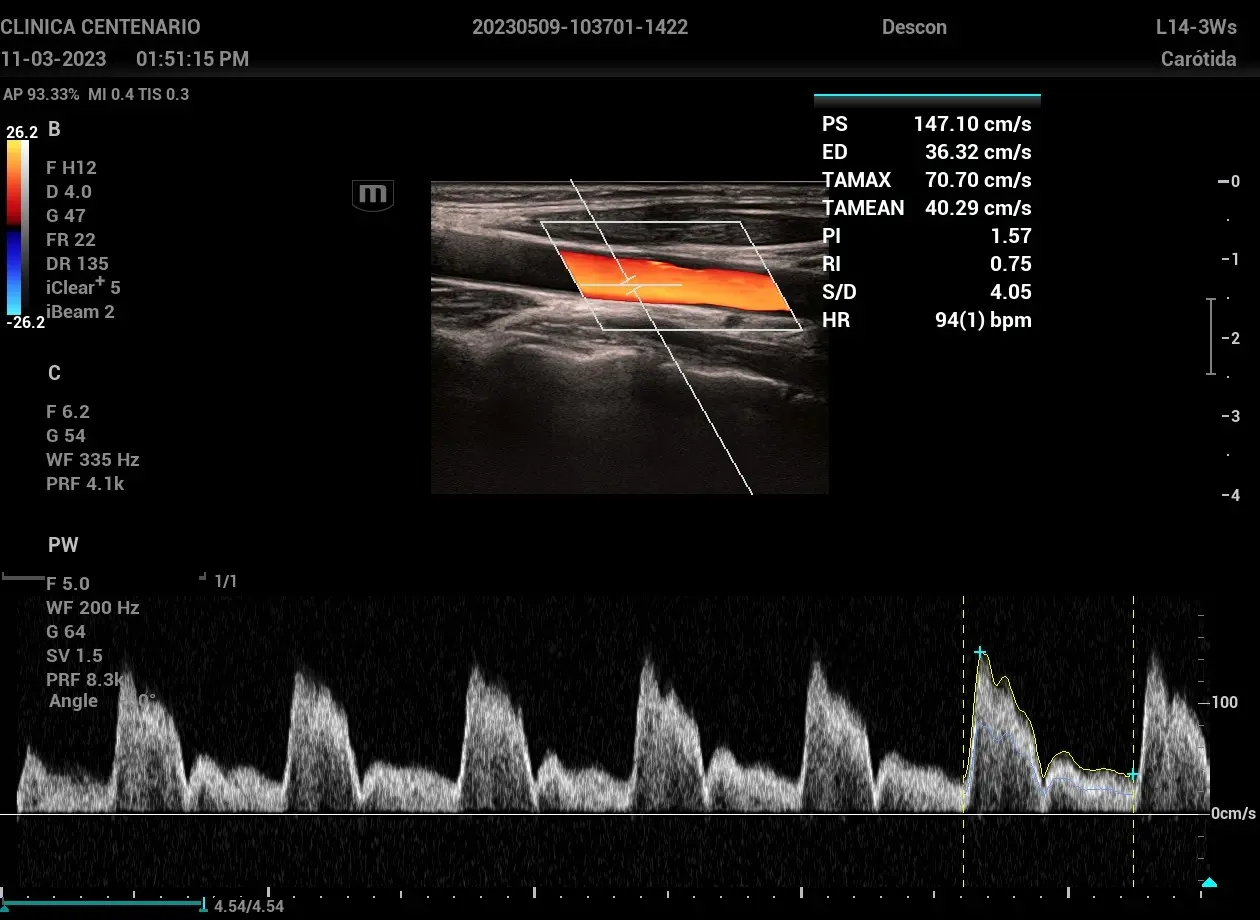

¿Busca evaluar la circulación sanguínea de manera precisa? ¿Busca obtener imágenes detalladas del flujo vascular en tiempo real, incluso en situaciones clínicas complejas? El ultrasonido Doppler es una de las herramientas diagnósticas más versátiles y seguras, ampliamente utilizada en especialidades como radiología, medicina vascular, cardiología y obstetricia.

El ultrasonido Doppler, una herramienta esencial para la evaluación vascular y hemodinámica, se puede ejecutar bajo 4 diferentes técnicas:

Su uso no se limita a una única especialidad, sino que se extiende a múltiples escenarios clínicos donde la evaluación del flujo vascular es determinante. Conozca a continuación las principales situaciones en las que se recomienda este tipo de estudio: